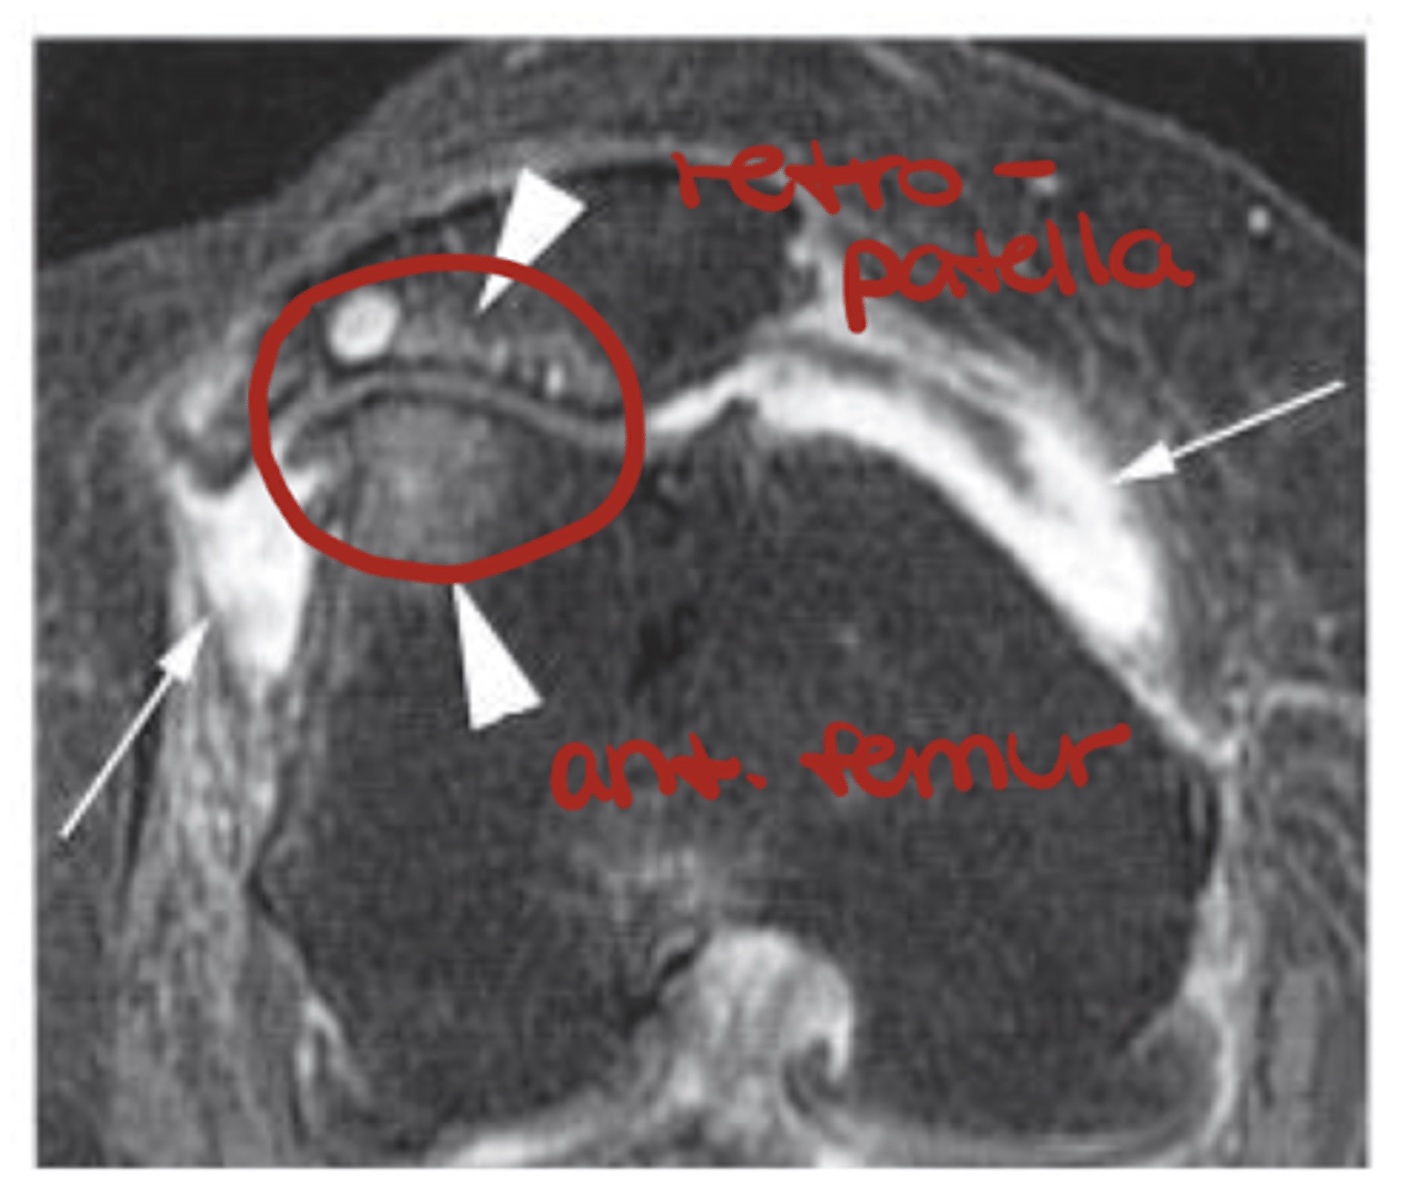

Sub-chondral edema/bone bruise (HUGE influence on rehab!!)

Define the pathology.

Synovitis surrounding the joint